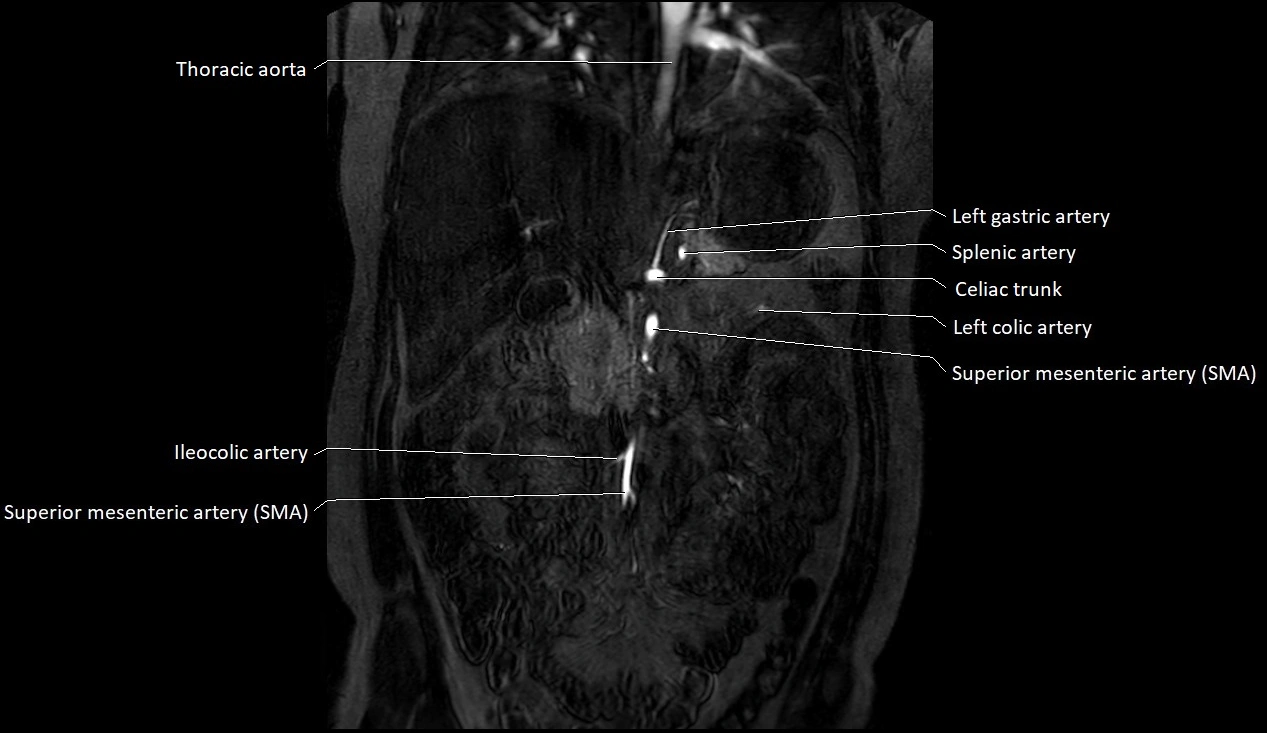

MRA (Magnetic Resonance Angiography):

• Contrast-enhanced MRA provides high-resolution imaging of the aorta and its branches

• Allows 3D reconstruction of visceral, parietal, and terminal branches

• Excellent for evaluating aneurysm size, dissection flap, stenosis, or preoperative planning

• Non-invasive alternative to conventional angiography